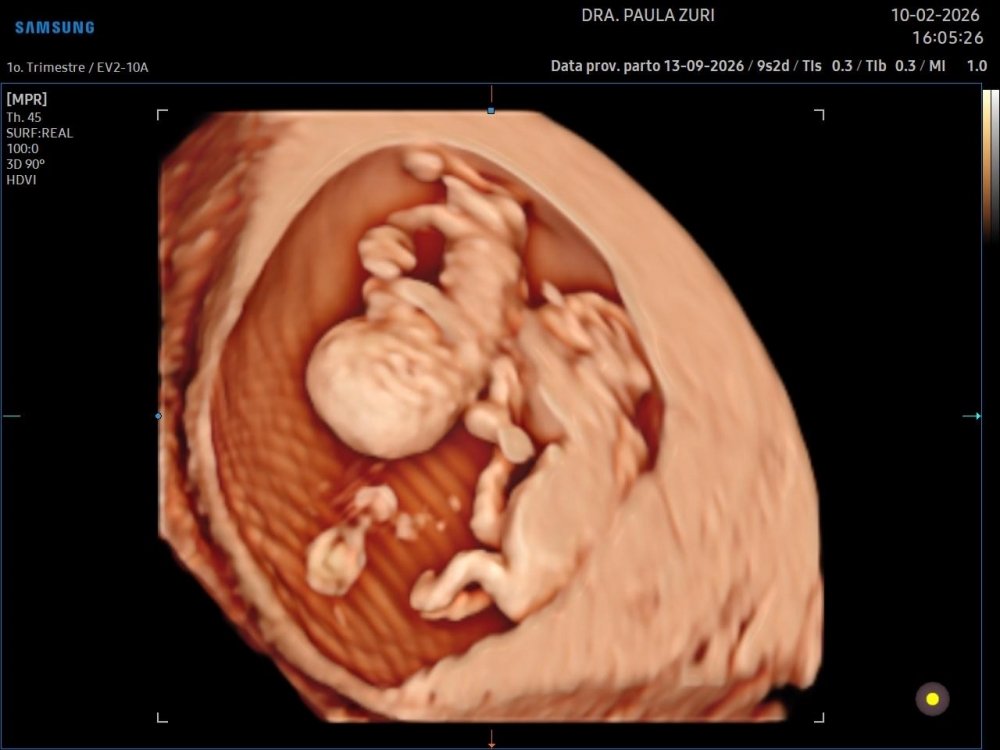

Nosso 1• Ultrassom 🫶🏼